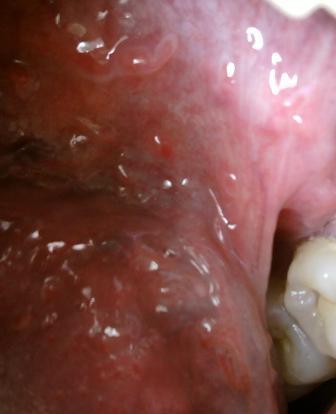

石家庄九州皮肤病医院 > 尖锐湿疣 > > > 尖锐湿疣患者如何饮食专家表示:在当检查出自己换上尖锐湿疣之后,应该及时去正规的 医院接受治疗,为了更好的治疗疾病,在积极接受治疗的同时也应该注意科学饮食,这对于疾病的治疗和康复你是很关键的。

尖锐湿疣患者如何饮食研究表明:患者多吃一些富含维生素和蛋白质高的食物,可以有助于疾病的康复。新鲜的水果和蔬菜患者应该多吃,平时也应该服用一些蜂蜜水,以提高身体免疫功能。饮食以清淡为主比较好,但是经常是辛辣刺激性的食物,经常抽烟喝酒对于病情的治疗和康复是很不利的。尖锐湿疣是一种危害很大的疾病,患病之后及时去正规的医院接受诊治是很关键的,以免把病毒传染给他人,害人害已。目前常用的治疗尖锐湿疣发方法主要有:激光疗法,光动力疗法,免疫细胞重组疗法,微波疗法,冷冻疗法,电灼疗法和手术疗法等等,但是每一种疗法在治疗上都是有各自的侧重点的,所以在这里建议大家应该听从主治医师的安排,对因对症标本兼治,才可以达到很好跑的治疗疾病的目的。